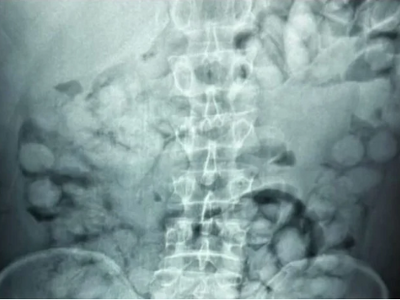

Κατά τον έλεγχο, οι αστυνομικοί εντόπισαν ύποπτα ευρήματα και ο άνδρας οδηγήθηκε άμεσα για ιατρικές εξετάσεις. Η ακτινογραφία που ακολούθησε αποκάλυψε πως είχε καταπιεί 100 κάψουλες κοκαΐνης, βάρους περίπου 11 γραμμαρίων η καθεμία.

Η συνολική ποσότητα του ναρκωτικού που κατασχέθηκε ξεπερνά το ένα κιλό, ενώ οι κάψουλες έφεραν ειδική επικάλυψη για να αντέξουν στο πεπτικό σύστημα.

Η Ελληνική Αστυνομία έδωσε στη δημοσιότητα χαρακτηριστικές εικόνες από τις ακτινογραφίες, ενώ η έρευνα συνεχίζεται για τον εντοπισμό πιθανών συνεργών του συλληφθέντος.